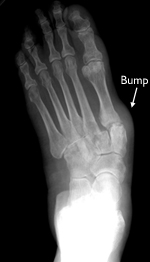

With RA, the ligaments that support the midfoot become weakened and the arch collapses. With loss of the arch, the foot commonly collapses and the front of the foot points outward. RA also damages the cartilage, causing arthritic pain that is present with or without shoes. Over time, the shape of the foot can change because the structures that support it degenerate. This can create a large bony prominence (bump) on the arch. All of these changes in the shape of the foot can make it very difficult to wear shoes.

This x-ray shows signs of RA of the midfoot. Note that the front of the foot points outward and there is a large bump on the inside and bottom of the foot.